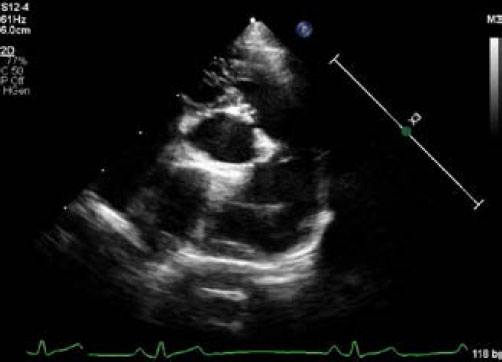

Transthoracic echocardiography (Affiniti 50; Philips Medical Systems, WA, USA) was performed with a sector-array transducer (4–12 MHz). An abnormal slit-like tunnel structure, 2.2 mm in internal diameter, connecting the ascending aorta to the left ventricle was detected above the sinutubular junction. The opening of this structure was located in the base of the ventriculoaortic junction between the anterior mitral leaflet and non-coronary cusp. The morphology and motion of both the mitral and arterial valves were normal, with no evidence of aortic stenosis, mitral regurgitation, or valvular vegetation (Supplementary video I). During the diastolic phase, a regurgitant jet was detected along the aortic cusps with a 2.8 m/second peak velocity and 32 mmHg pressure gradient and along the anterior mitral leaflet with a 2.3 m/second peak velocity and 22 mmHg pressure gradient from the tunnel opening to the left ventricle (Fig. 2, Supplementary Video I). There was mild left ventricular eccentric hypertrophy with an internal diameter in diastole and systole of 23.7 mm (reference range: 16.70–18.93 mm) and 12.2 mm (reference range: 9.04–10.98 mm), respectively. The normalized value of the end diastolic left ventricular interior dimension was 1.63 (reference range: <1.7). The interventricular septum thickness in diastole and systole was 4.9 mm (reference range: 5.70–7.53 mm) and 6.1 mm (reference range: 8.60–10.64 mm), respectively. The thickness of the left posterior wall during diastole and systole was 4.6 mm (reference range: 4.53–6.03 mm) and 7.0 mm (reference range: 7.97–9.55 mm), respectively. Left ventricular systolic function was normal based on fractional shortening of 48.5% and an ejection fraction of 61.6% obtained by Simpson’s method of discs.

Fig. 2. Echocardiography of right parasternal five chamber view (A–C), oblique right parasternal short axis view of the heart base (D), and oblique left apical long axis view (E,F). (A, B) an abnormal slit-like tunnel structure (arrowheads) next to the aorta is shown. (A,C) The opening of this tunnel structure is located in the base of the ventriculoaortic junction between the non-coronary cusps and anterior mitral leaflet. (D–F) during the diastolic phase, a regurgitant jet is detected along the aortic cusps (black arrows; 2.8 m/second peak velocity, 32 mmHg pressure gradient) and along the anterior mitral leaflet (white arrows; 2.3 m/second peak velocity, 22 mmHg pressure gradient) from the tunnel opening to the left ventricle.